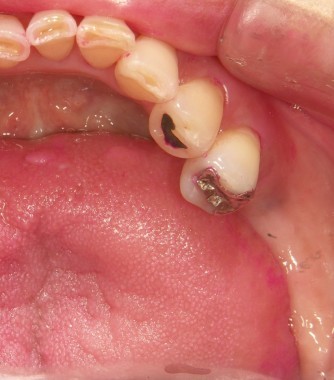

インプラントの術前・術後 Nさん